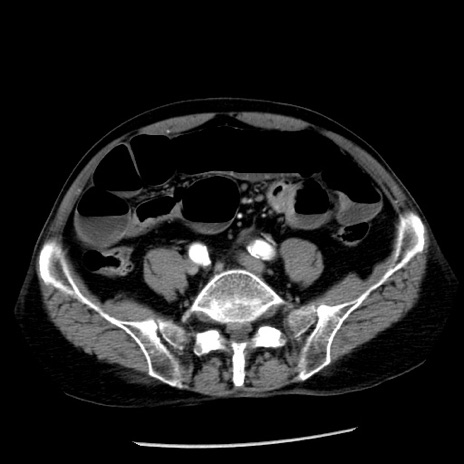

冠状断像

【症例】80歳代男性

【主訴】嘔吐

【現病歴】昨晩2回嘔吐あり、今朝になっても嘔吐あり。来院。

【既往歴】胃潰瘍

【身体所見】意識清明、BT 37.6℃、BP 166/95mmHg、HR 100bpm、SpO2 97%、腹部:平坦・軟、腸蠕動音聴取良好、圧痛なし。

【データ】WBC 21900、CRP 1.46